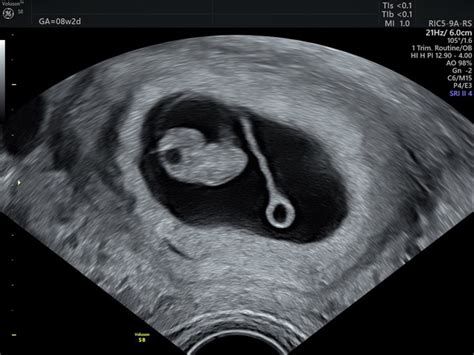

V 32. tednu nosečnosti je otrokovo telo skoraj v celoti oblikovano in razvoj organov je končan, le par stvari še manjka, da bodo svojo funkcijo opravljali optimalno. Še vedno pridobiva podkožno maščobo, zaradi katere postaja nekoliko bolj zalit in izginjajo še preostale kožne gube. Otrok še naprej trenira in razvija tudi svoja čutila, ki mu bodo po rojstvu omogočila zaznavanje in odzivanje na svet okoli sebe.

Ker otroku v maternici že primanjkuje prostora, je vedno bolj tesno zvit v tako imenovanem fetalnem položaju, z nogami privitimi k prsnemu košu. Otrokove noge so tesno privite k telesu, otrok pa občasno sesa svoj nožni palec in tako še naprej uri sesalni refleks. Njegove roke so prekrite čez trebušček, med njima pa je popkovina, ki jo otrok občasno močno potegne. Na tej stopnji je otrok skoraj popolnoma razvit in je že videti kot majhen novorojenček.

Velikost ploda v 32. tednu nosečnosti je primerljiva z velikostjo listnatega ohrovta. Trenutno si v osmem mesecu nosečnosti.